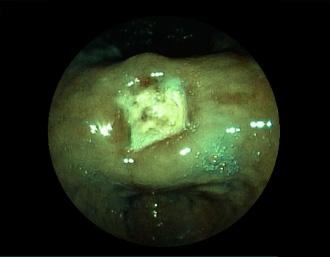

症例1:胃潰瘍(37才、男性)

①胃潰瘍(Stage A1)

健診:胃レントゲン検査で、胃角部ニッシェを指摘され当院受診。

胃角部小弯に、深くて大きな、大きさ約10mmの胃潰瘍(stage 1)

があり、潰瘍底は一部白苔はみ出しを認める。エソメプラゾールマグネシウム水和物投薬で治療開始しました。

(FICE+インジゴカルミン散布画像)